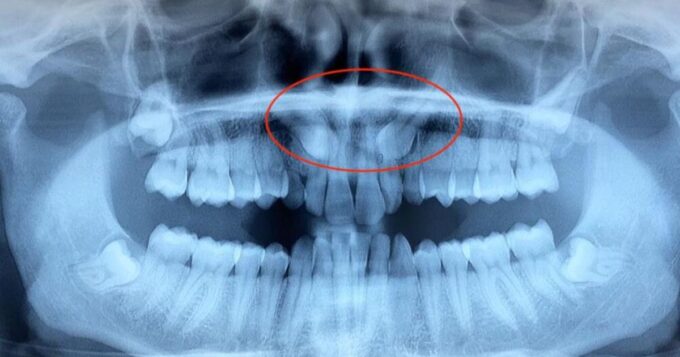

Un dente permanente non dovrebbe mai muoversi. Quando accade, è spesso segno che qualcosa non va nel supporto che lo tiene ancorato all’osso. La causa più frequente? La parodontite: una malattia che colpisce gengive, osso e legamenti che sostengono i denti. Denti che si muovono: i sintomi Il dente che si muove, raramente è un…